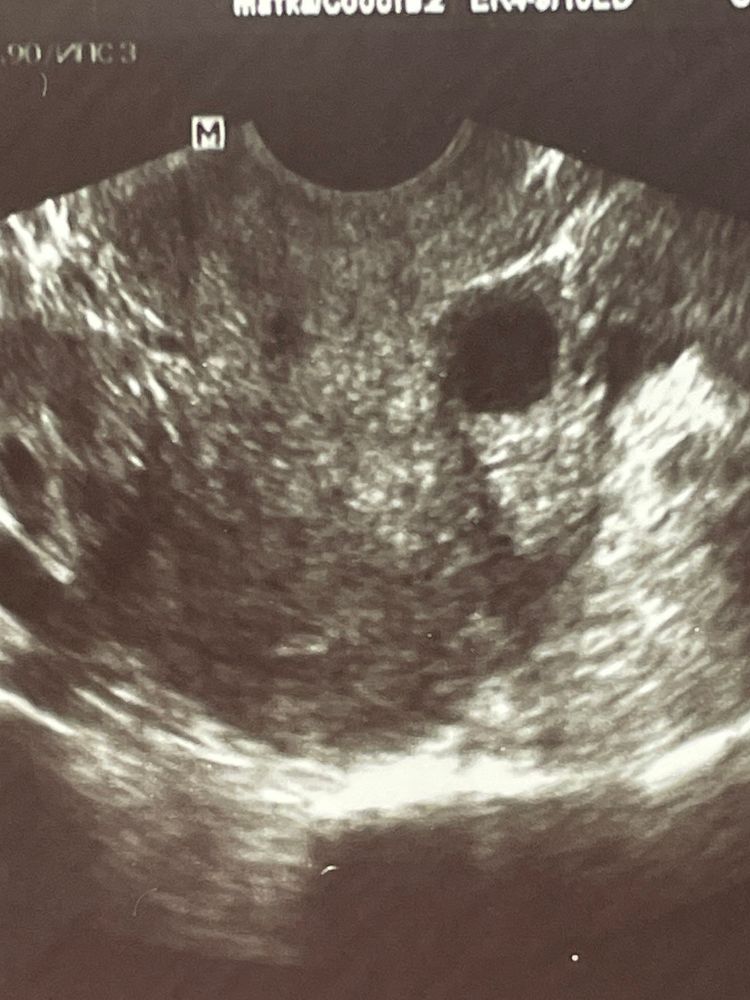

2 фото. Образование так же 10 мм - полип под вопросом? (25 апреля)